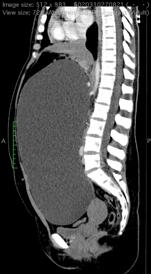

n prezenta serie de cazuri, au fost incluse pacientele din Institutul Oncologic „Prof. Dr. Ion Chiricuță” Cluj-Napoca cu carcinom seros ovarian de grad inalt in stadiul initial al bolii III sau IV (avansat). Toate pacientele au fost chimiotratate neoadjuvant in institutie si ulterior au beneficiat de secventa chirurgicala a tratamentului oncologic

prin citoreductie de interval. În condiții sterile, produsul verde indocianină (Verdye, 25 mg sub formă de pulbere) a fost reconstituit cu 5 ml apă distilata și utilizat imediat. Administrarea ICG a fost efectuată intravenos sub formă de bolus rapid de 0,1 mg/kg greutate corporală. Sistemul de imagistică utilizat a fost Zeiss Opmi Pentero 800 echipat cu modul de fluorescență intraoperator Infrared 800. După fiecare bolus de ICG, suprafața peritoneală a fost inspectată pentru anomalii în intensitatea fluorescenței, definite ca zone de fluorescență hipointensă sau hiperintensă. care au fost excizate și trimise pentru examinare histopatologica.

Cincisprezece paciente din Institutul Oncologic „Prof. Dr. Ion Chiricuță” Cluj-Napoca cu varsta mediana de 56 de ani (38-71 de ani) au fost incluse in prezenta serie, din care 10 cazuri au fost clasificate ca stadiul IIIB-C (66,7%), iar 5 au fost clasificate ca stadiul IVA-B (33,3%). După caracterizarea moleculară, 7 paciente aveau o mutație BRCA1 sau BRCA2 (46,6%), iar 8 pacienți erau de tip wild-type (fara alele cu semnificatie patologica). Opt pacienti au fost catalogati ca purtatori a unui deficit de recombinare omoloaga (HRD pozitive) (53,3%). Toți pacienții au beneficiat de 4 pana la 7 cicluri de chimioterapie neoadjuvanta in cadrul Institutului. Durata operativă medie a interventiilor chirurgicale a fost de 135 minute. Citoreductia completa a fost realizata la 11 pacienți (73,3%).

După fiecare bolus, timpul mediu de fluorescență intraoperatorie pentru identificarea zonelor suspecte a fost de 3,59 minute. Fiecare pacient a avut un timp mediu de fluorescență combinat de 5,74 minute. Pentru fiecare caz, o medie de 2,6 probe peritoneale suspecte suplimentare au fost identificate, cu dimensiunea medie de 15,9 mm. Au fost identificate un număr suplimentar de 39 de probe peritoneale suspecte, 16 (41%) dintre acestea confirmând focare maligne microscopice de cancer ovarian seros de grad înalt. Prin urmare, numărul total de leziuni rezecate a crescut cu 38%, iar numărul total de leziuni maligne confirmate histologic rezecate a crescut cu 25%. Patru din 13 (30,8%) zone ICG hiperintense și 12 din 26 (46,2%) zone ICG hipointense au fost confirmate ca fiind maligne. Pentru subgrupul de pacienti BRCA1/2 pozitivi, rata de pozitivitate pentru focarele maligne a fost de 3 din 7 (42,9%) zone ICG hiperintense și 6 din 10 (60%) zone ICG hipointense. În mod similar, pacientelor cărora li s-a administrat bevacizumab neoadjuvant pozitivitatea reală pentru focarele maligne a fost de 3 din 4 (75%) zone ICG hiperintense și 8 din 11 (72,7%) zone ICG hipointense. Durata mediană de urmărire a fost de 36,6 luni, timp in care 7 pacienți au recidivat (46,7%) și 3 pacienți au murit (20%). Supraviețuirea medie fără progresie a fost de 34,2 luni iar supraviețuirea globală medie a fost de 42,4 luni.